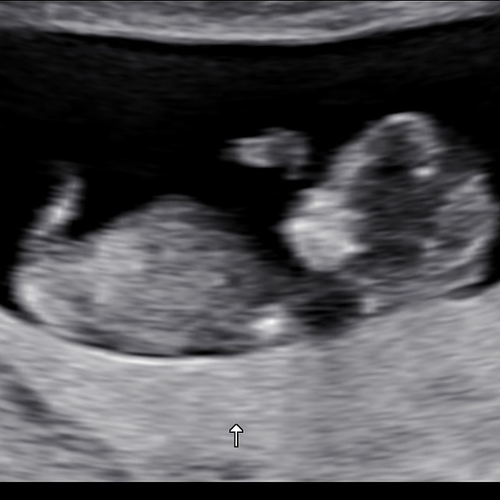

Jongen of een meisje? Wat denken jullie? 😁

Volgens mij zie ik een pipi 💙